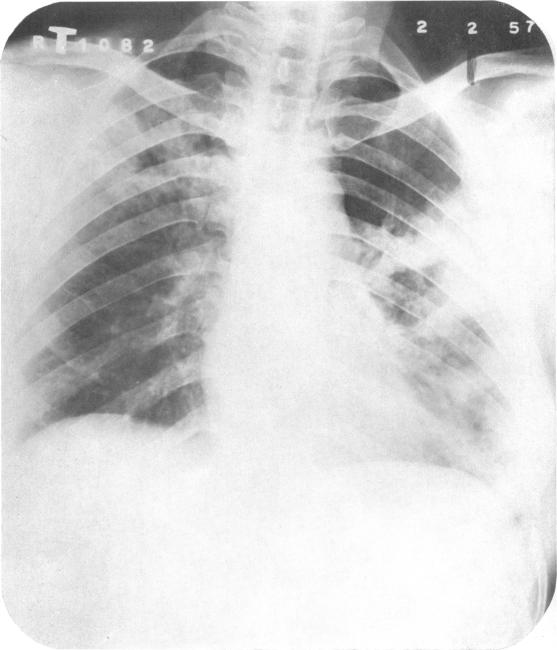

In India, as in most under-development countries, the tuberculosis problem is aggravated by an acute shortage of sanatorium beds. The number of active cases of tuberculosis in the country has been estimated at 2 (1/2) million, but only 23 000 tuberculosis beds are available. In these circumstances great importance attaches to the possibility of applying mass domiciliary chemotherapy as a substitute for sanatorium treatment in cases of pulmonary tuberculosis. The findings of the present study, based on a comparison of the two types of treatment over a period of 12 months, show that despite the manifest advantages of sanatorium care-rest, adequate diet, nursing and supervised medicine-taking-the merits of domiciliary chemotherapy are comparable to those of sanatorium treatment, and that it would therefore be appropriate to treat the majority of patients at home, provided an adequate service were established.